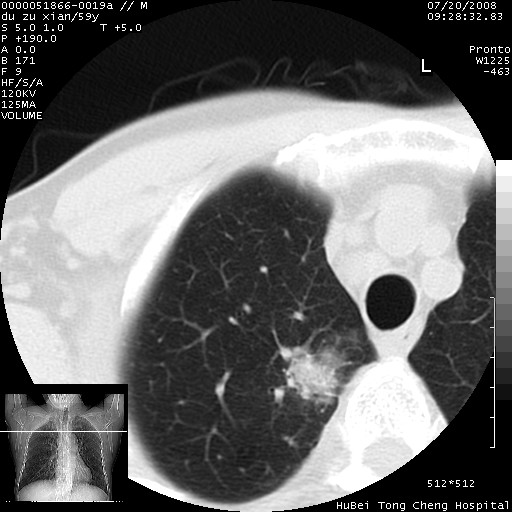

以下是引用宇宙ct在2008-8-25 23:21:00的发言:[br]右肺周围性肺癌并肋骨转移,纵隔淋巴结转移。

以下是引用zsl6918在2008-8-25 22:40:00的发言:[br]右肺周围性肺癌并肋骨转移,纵隔淋巴结转移。

以下是引用zy_zj在2008-8-26 15:24:00的发言:[br]单从病变本身,我倾向良性炎性病变,但肋骨转移了,所以说是考虑右肺周围性肺癌并肋骨、纵隔淋巴结转移可能性大。